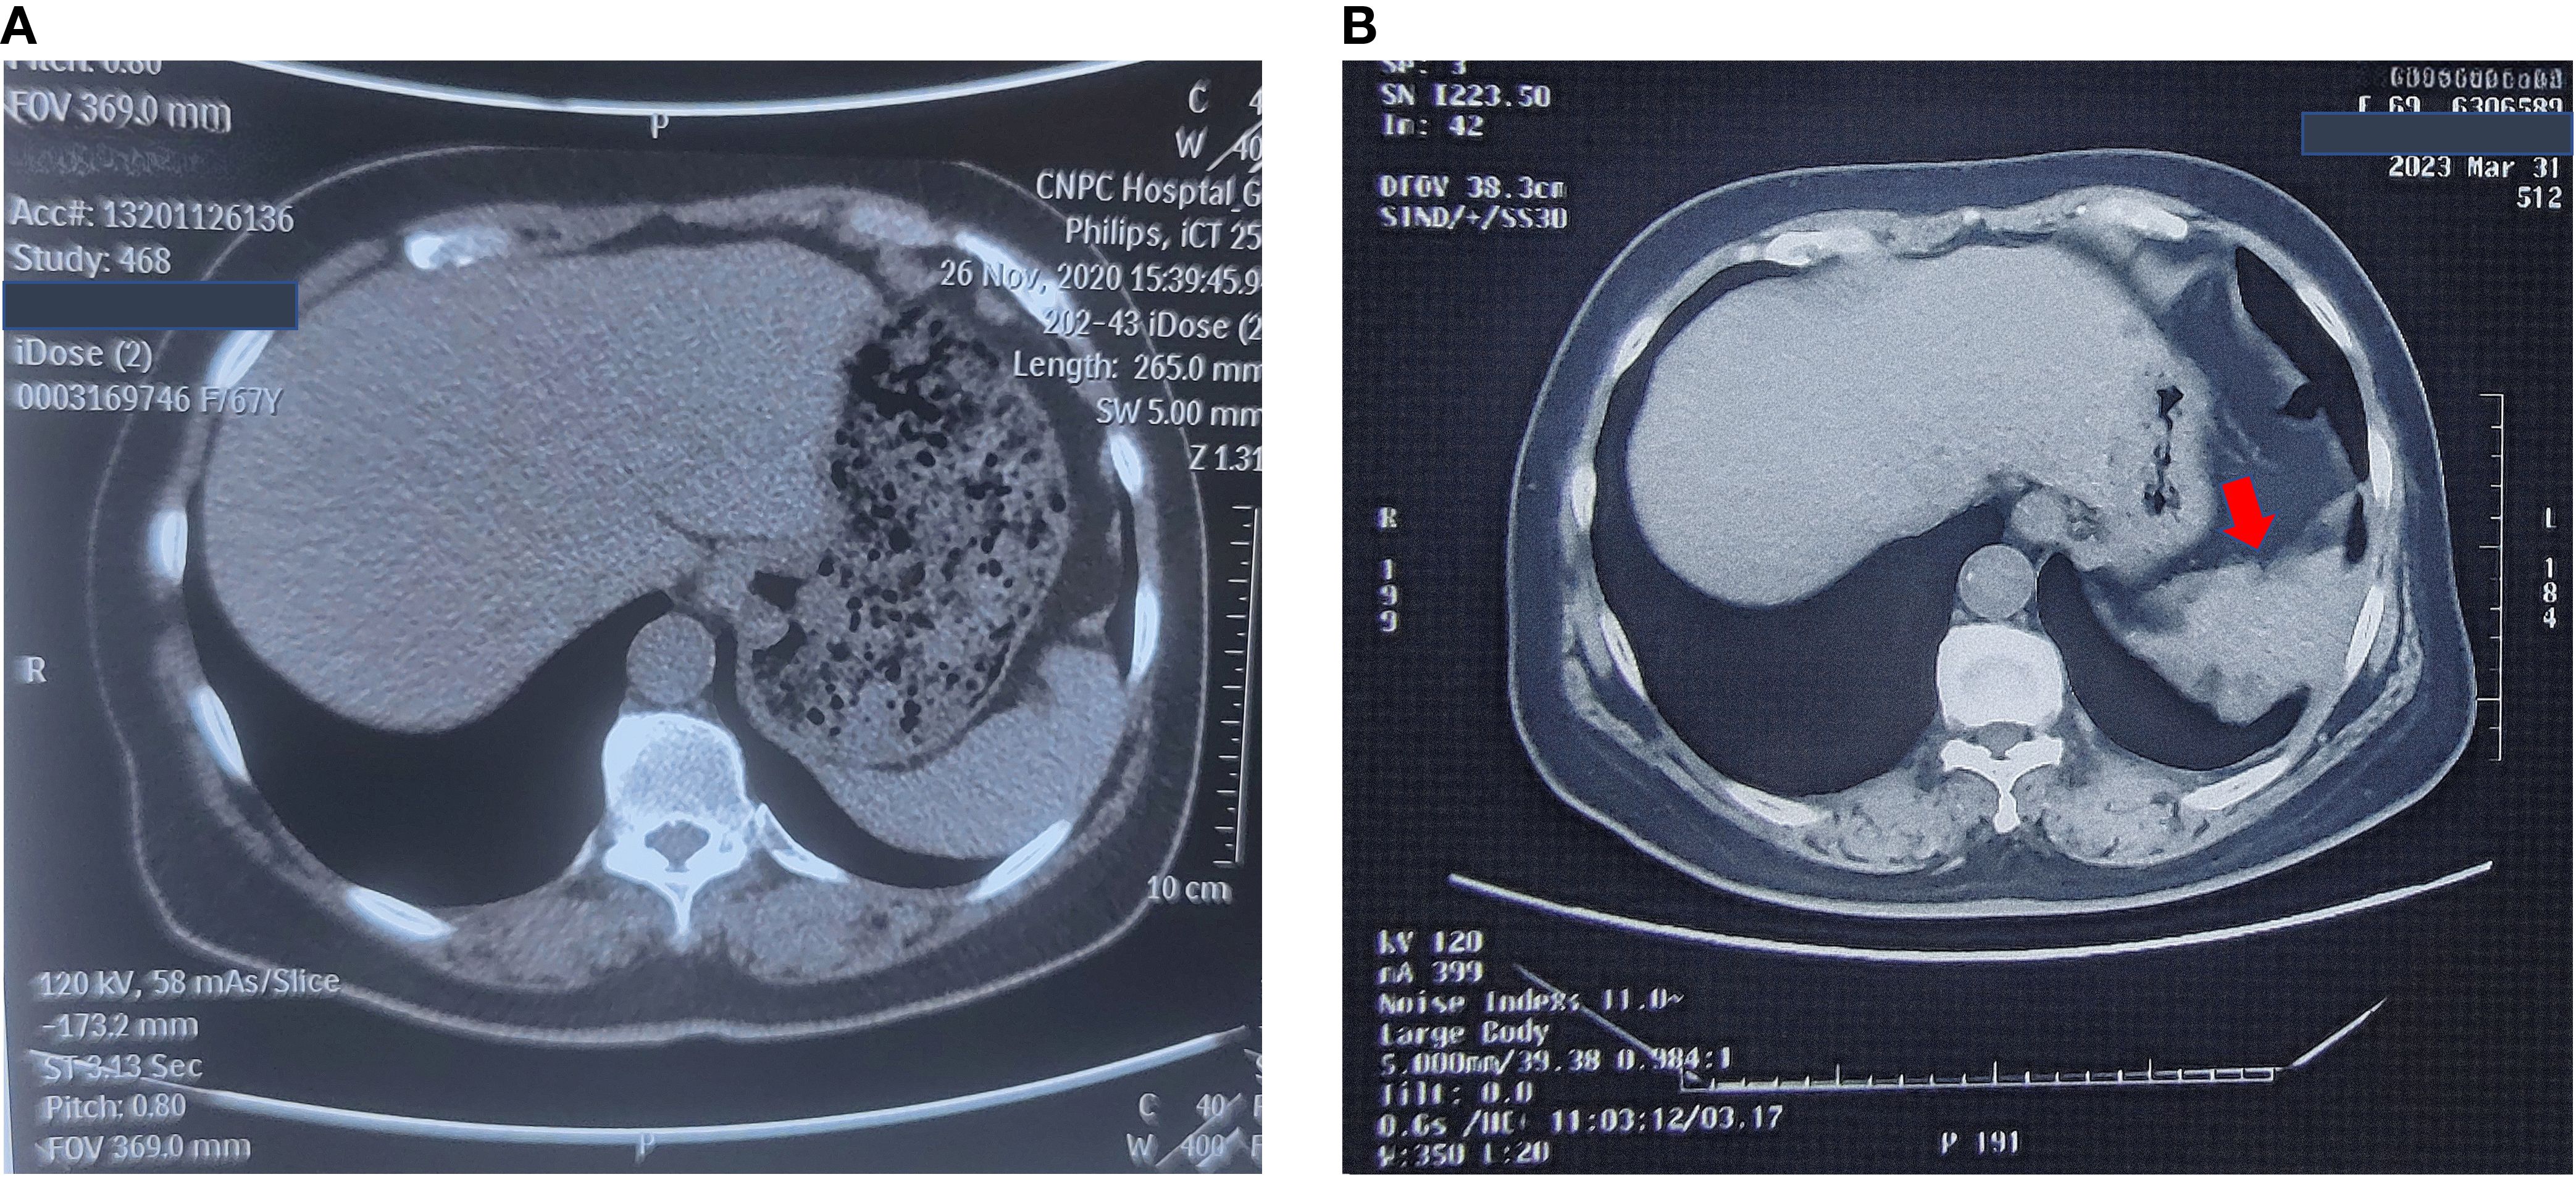

On November 13, 2023, her carcinoembryonic antigen (CEA) level was 43.52 ng/ml (normal range = 0–5 ng/ml), CA19–9 was 387 U/ml, and neuron-specific enolase (NSE) was 17.3 ng/ml (normal range = 0–15.2 ng/ml). Enhanced abdominal and pelvic CT revealed post-polypectomy changes in the stomach, with no obvious wall thickening or abnormal enhancement of the gastric wall. A spindle-shaped lesion with soft tissue density was observed below the left diaphragm, measuring approximately 5 cm × 1.5 cm. The lesion exhibited heterogeneous enhancement, smeared-out boundaries, and indistinct separation from the diaphragm. The spleen was shoved. The lesion was highly suspicious for a mesenchymal tumor, although malignant metastasis could not be ruled out. The left pleura appeared slightly thickened, and a patchy consolidation was noted adjacent to the pleura in the lower lobe of the left lung. On December 11, 2023, 18F-fluorodeoxyglucose (FDG) PET-CT revealed an irregular soft tissue mass in the left diaphragmatic area with a maximum standardized uptake value (SUVmax) of 11.4, which measured approximately 3.9 cm × 3.4 cm × 2.4 cm. The lesion was growing toward the diaphragm; and its boundaries with the diaphragm and the spleen were unclear. PET-CT also demonstrated local thickening of the adjacent left pleura with a mildly increased radiotracer uptake (SUVmax = 2.3), as well as local discoid atelectasis of the lung. No enlarged or hypermetabolic lymph nodes were observed in the retroperitoneum or abdominal cavity. The lesion was considered suspicious for a mesenchymal tumor. The CT and PET-CT images are shown in Figure 2. However, the patient did not undergo a biopsy due to her Rh-negative blood type.

CT and PET scans showing different perspectives of abdominal structures. Panel a: Coronal CT scan with a red arrow indicating the mass near the spleen. Panel b: Axial CT scan with a red arrow pointing to a mass near the spleen. Panel c: Three images from a PET scan showing hypermetabolic mass, marked with red arrows.

Figure 2. Enhanced CT and PET-CT of the left subdiaphragmatic mass. (A) Coronal view of enhanced CT of the left subdiaphragmatic mass on November 14th, 2023. (B) Axial view of enhanced CT of the left subdiaphragmatic mass on November 14th, 2023. (C) PET-CT of the left subdiaphragmatic mass on December 12th, 2023.